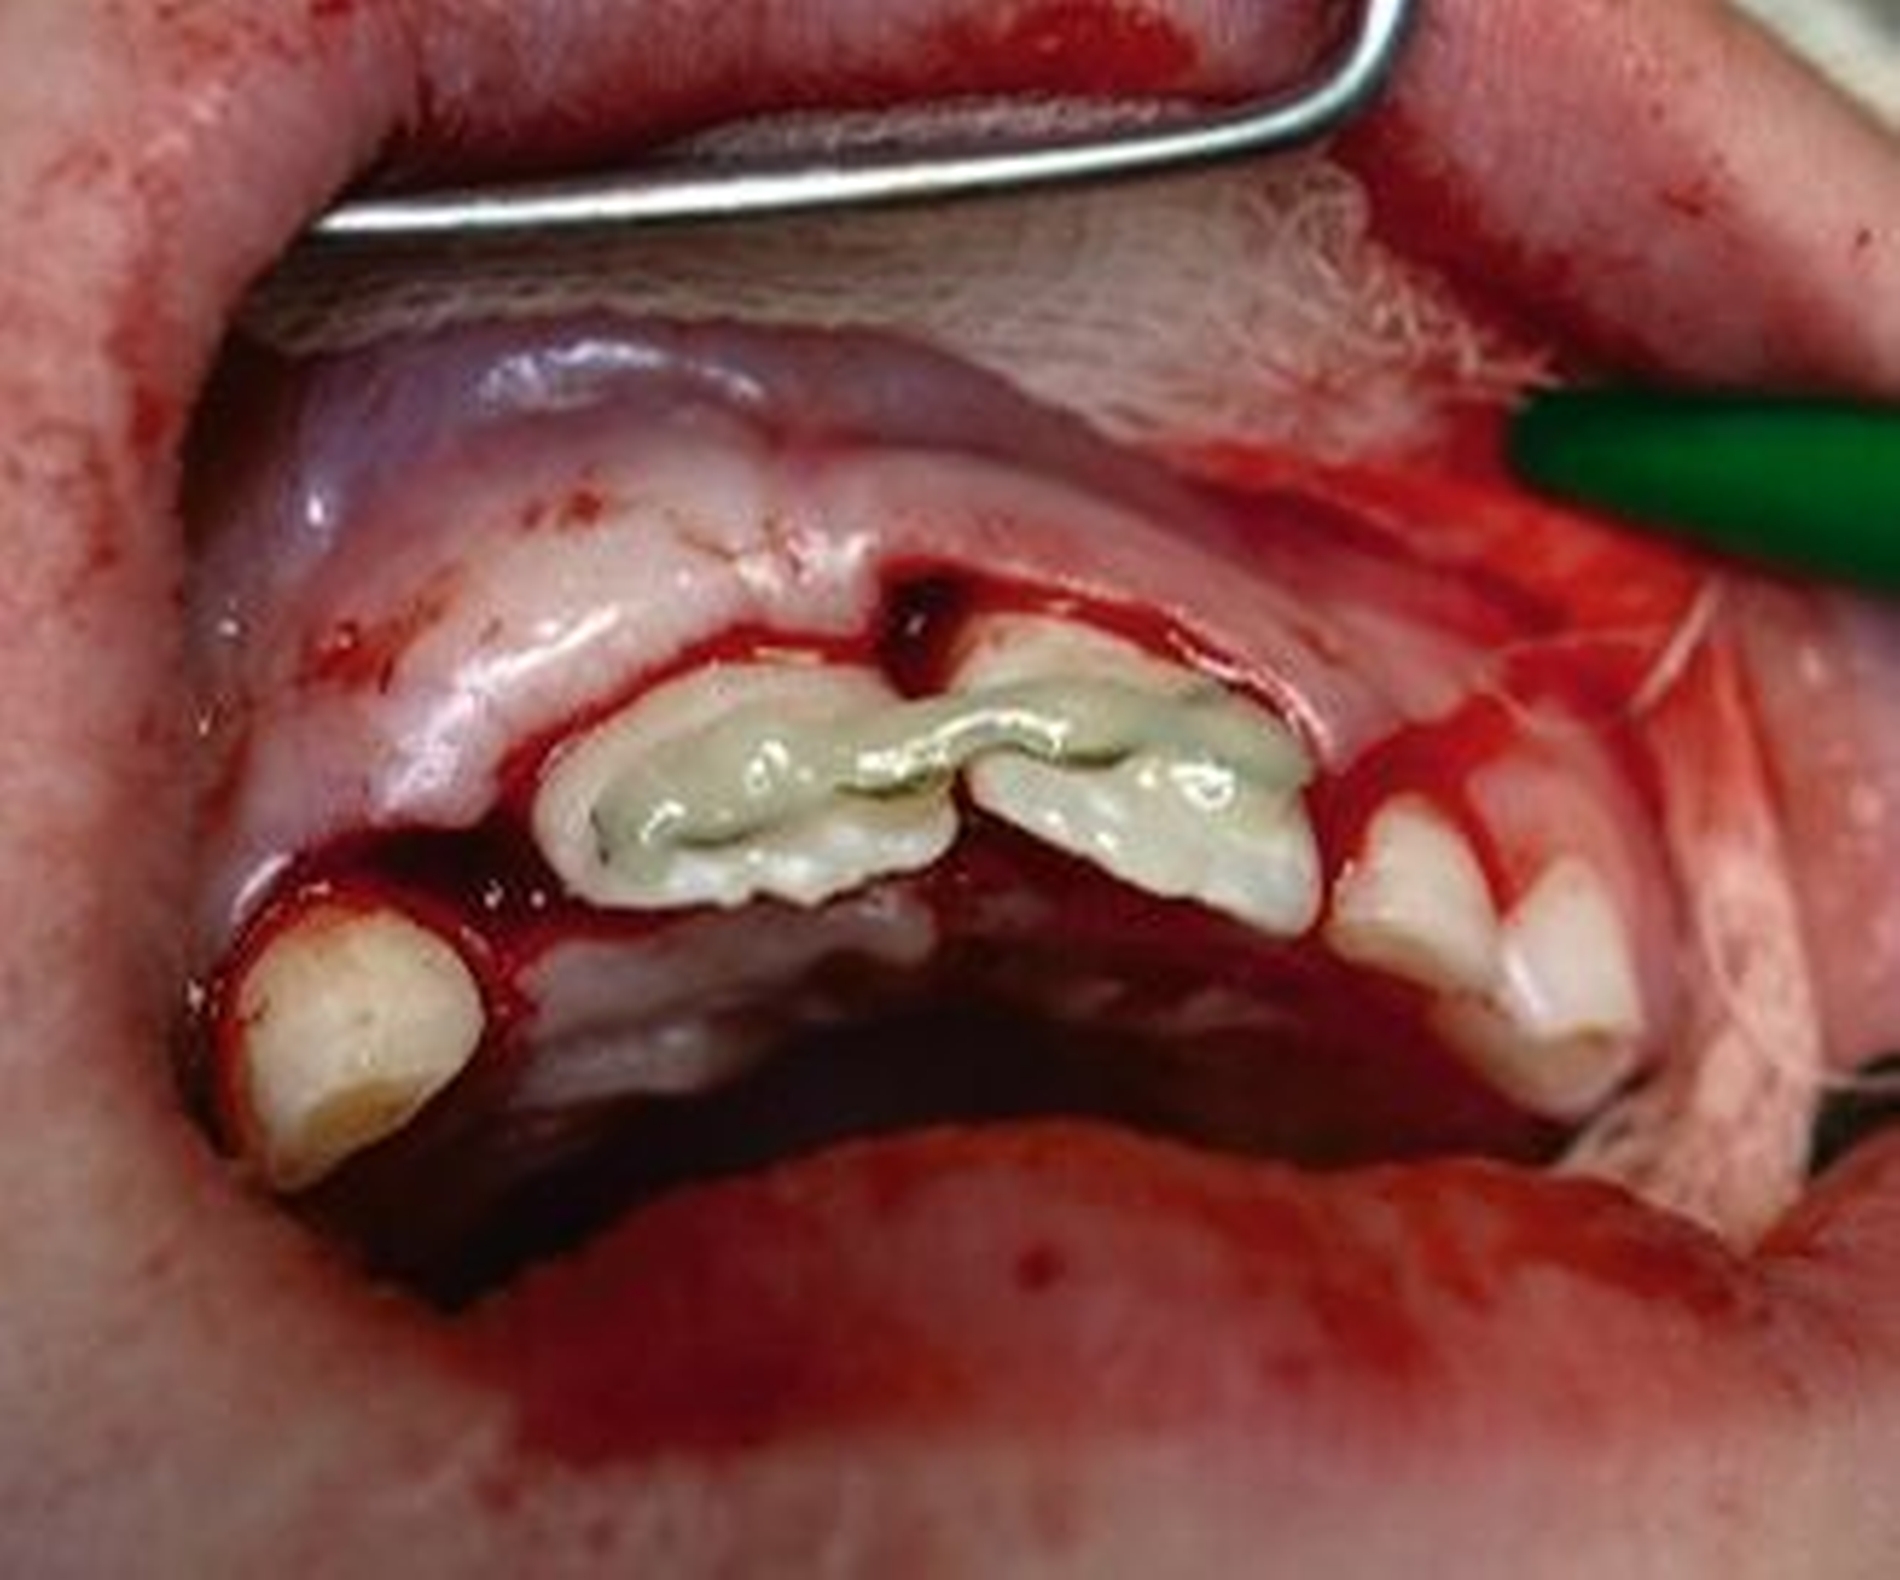

Nach der Einschätzung der Zellvitalität auf der oben genannten Basis folgt die therapeutische Intervention im Sinne der Replantation des betroffenen Zahnes in die gespülte Alveole (vorsichtige Entfernung des Blutkoagulums) mit steriler physiologischer Natriumchloridlösung. Schließlich muss die Replantation schonend erfolgen, da immer mit daran gedacht werden muss, dass es im Rahmen des Traumas zusätzlich zu einer Schädigung des Alveolarknochens gekommen sein kann (Abbildung 1). Diese Schädigung kann eine vollständige oder teilweise Alveolarfortsatzfraktur sein, die entsprechende Beachtung finden sollte. Im Anschluss erfolgt die Schienung des betroffenen Zahnes an den Nachbarzähnen. Dabei sollte ein Zeitraum von ein bis drei Wochen eingeplant werden (Tabelle 1).

Die Replantation sollte langsam und mit wenig Druck erfolgen, um eine zusätzliche Schädigung des Wurzelzements zu vermeiden. Anschließend sollte eine flexible Schienung des Zahnes erfolgen (Empfehlung 50) [Kahler et al., 2016].